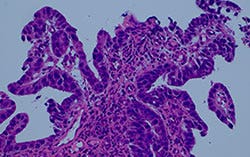

그림 4: 필터 장착 할로겐램프와 일반 LED 및 트루컬러 LED의 비교

트루컬러 LED(특허출원 중)는 Olympus의 혁신을 위한 헌신의 산물이며, 병리학자에게 익숙한 할로겐램프 및 필터 방식과 같은 연색성 및 광도 성능을 제공합니다. 이 새로운 광원의 고품질 조명은 시중에 나와 있는 밝은 LED로는 달성할 수 없습니다. 이 백색 LED 광원이 탑재된 BX53 현미경은 다른 관찰 방법뿐 아니라 투과 명시야 현미경 검사에도 유리합니다. 강렬한 밝기 수준 덕분에 동시 관찰을 위한 멀티 헤드 논의 및 교육 시스템에 활용할 수 있으며, 연색성이 높은 백색 LED가 신뢰성 있는 샘플 관찰을 원하는 병리학자들이 필요로 하는 색상 무결성 성능을 제공합니다.